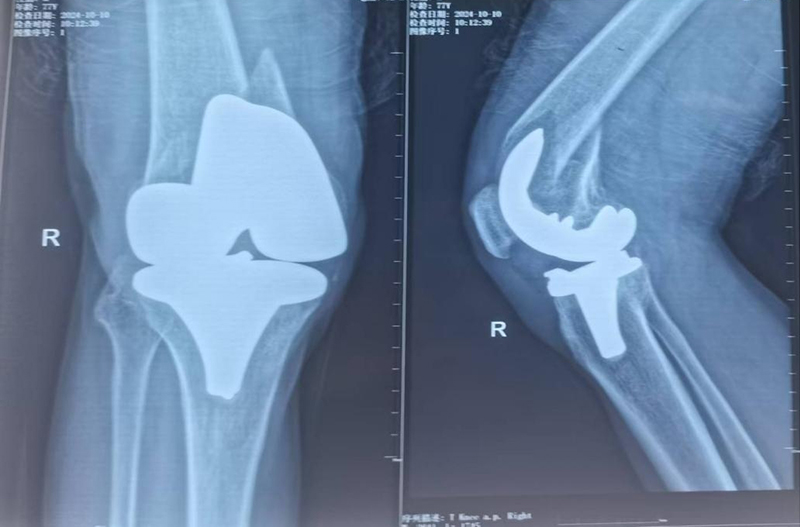

膝关节置换术后假体周围骨折特殊假体返修术后

手术由骨科专家许立新主任亲自主刀,在手麻科医护人员的全力配合下,顺利开展。手术过程中,发现膝关节假体彻底松动,胫骨假体也发生了松动,这再次证实了术前计划的合理性,去除松动假体后,安装特制肿瘤膝关节,手术过程非常顺利,仅用时86分钟。